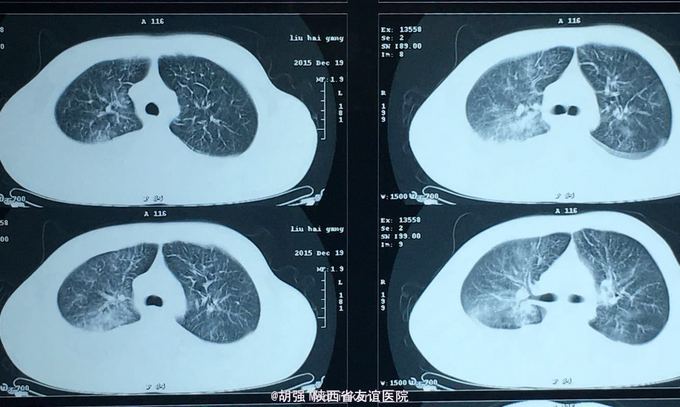

查体:口唇无发绀,咽充血,双侧扁桃体2度大,表面可见脓胎。两肺呼吸音粗糙,可闻及管状呼吸音。余查体无明显异常。 辅助检查:血常规提示白细胞及血小板明显低于正常值,肝功提示转氨酶升高。凝血系列:PT、APTT时间明显延长。T sport试验弱阳性。10月份胸部CT平扫未见明显异常。10月26日及12月12日胸片未见明显异常。12月19日胸部CT提示:两肺斑片状阴影,两侧胸腔积液。